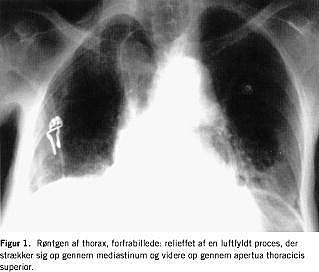

Blodtrykket var 220/120. Et elektrokardiogram (ekg) viste sinustakykardi, frekvens 134, uden tegn på iskæmi. Patientens saturation ved ankomsten var 92% på 8 l ilt pr. min. A-punktur viste svær respiratorisk acidose, pH=7,13. Røntgen af thorax viste en dilateret subdiafragmalt beliggende ventrikel og en dilateret colonslynge i mediastinum strækkende sig helt op i halsregionen, der sås normale lungefelter (Figur 1 og Figur 2 ).

I den foreliggende sygehistorie har der formodentlig været tale om herniering gennem hiatus oesophageus. Dette blev vurderet af en speciallæge i radiologi ud fra røntgen af thorax i to planer.